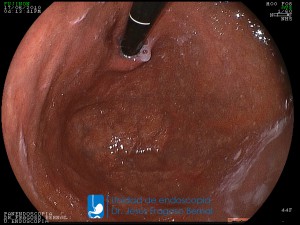

La Unidad de Endoscopía fue creada en 2002 por el Dr. Jesús Fragoso Bernal, es pionera en el estado por la utilización de la tecnología más avanzada, que nos permite ofrecer servicios integrales de diagnóstico y tratamiento para las enfermedades del aparato digestivo.

"La Unidad de Endoscopía se ha caracterizado por un progreso continuo desde su inicio marcando la pauta en los procedimientos endoscópicos en el estado de Tlaxcala y estando siempre a la vanguardia tecnológica."

Dr. Jesús Fragoso Bernal